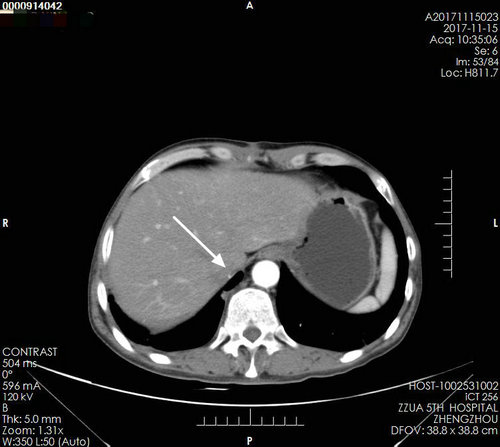

▲ 术后复查影像

术后复查:下腔静脉通畅,腔内CT值均匀,未见填充物,右肾区由肠管填充,未见肿瘤残留及复发。